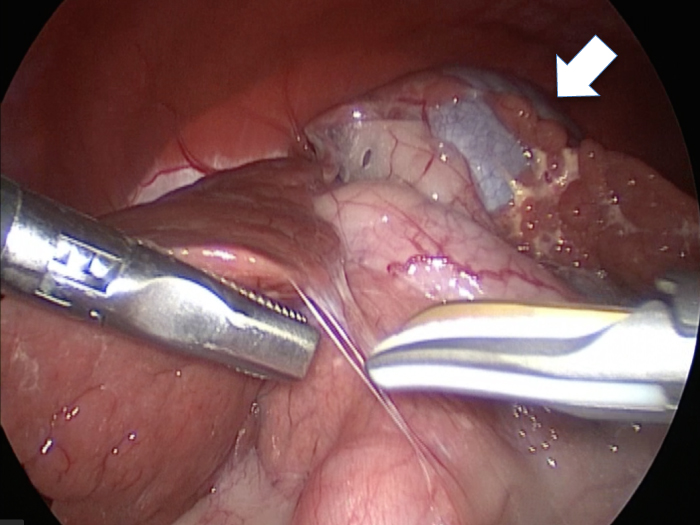

丁寧に丁寧に出血をコントロールしながら少しずつ手術をすすめていきます。

このように癒着しているときはギリギリで剥がすとひどく出血をおこすことがあるので無理にはがそうとしないで、脂肪の血管に注意しながら脂肪ごと剥がしていきます。

胆嚢を少しずつ丁寧に肝臓から剥がしています。